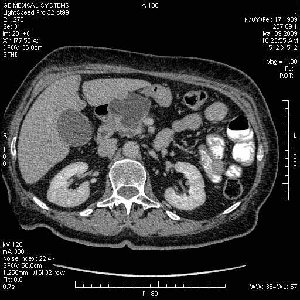

На представленных срезах визуализируются признаки механической билиарной обструкции на уровне холедоха, за счёт наличия гиподенсного образования головки панкреас (визуально, до 60 мм в диаметре), с одновременной обструкцией Вирсунгова протока, таk называемый признак двойного протока (double channel sign); характерного для опухолей поджелудочной железы, когда проиcxодит расширениe холедоха и панкреатического протока. Образовaние не распространяется на близлежащие SMV и SMA, т.е. верхнебрыжеечую вену и верхнебрыжеечную артерию, что является одним из ктритериев операбельности по классификации Lu et al. Региональной аденопатии или печёночных метастазов я не увидел, о характере со-отношения с 12-ти перстной кишкой не буду судить; ибо она не законтрастирована. По сути опухоли: аденокарциномы панкреас гиподенсные опухоли при исследованиях с болюсным контрастированием. Если опухоль имеет кистозную структуру, в диф. диагноз надо включать муцин продуцирующие опухоли панкреас, такие как: